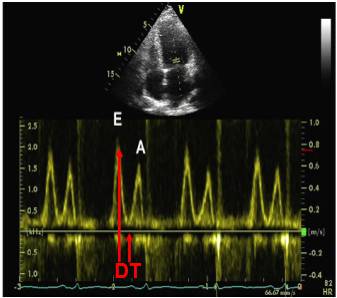

9、HFpEF—舒张功能负荷试验

●适用于静息状态下舒张功能轻度异常伴LV充盈压正常,但却出现难以解释的劳力性呼吸困难患者

●方法:仰卧踏车运动方案、多巴酚丁胺负荷试验

●标准:负荷后E/e’>10,DT缩短>50ms

●局限性:临床资料缺乏;伴随病变:如局限性LV功能异常、二尖瓣疾病、房颤

9、二尖瓣口舒张期血流频谱指标2

③限制性心肌病:二尖瓣口、肺静脉血流及组织多普勒参数:DT缩短140ms、E/A>2.5、E/e’升高>15